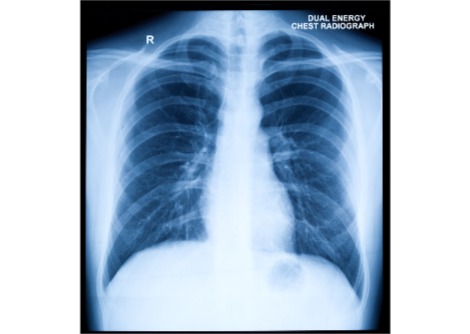

العديد من علاجات السرطان الحالية تجعل المرضى مرضى للغاية لأن حتى العلاجات الأكثر استهدافًا تقتل الخلايا السليمة وكذلك الخلايا السرطانية . لكن نوعًا جديدًا من العلاج يُسمى بالمقترِن المشع يحظى باهتمام أطباء الأورام . يجمع هذا النوع من الأدوية بين الإشعاع وعامل استهداف الورم ويمكن أن يغير مستقبل رعاية مرضى السرطان ، وفقًا لقصة الغلاف في Chemical & Engineering News ، وهو منفذ إخباري مستقل للجمعية الكيميائية الأمريكية.